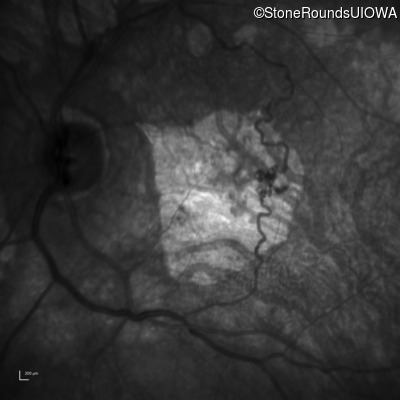

Infrared Fundus Photograph - Right - 20/125 -2

Exemplar